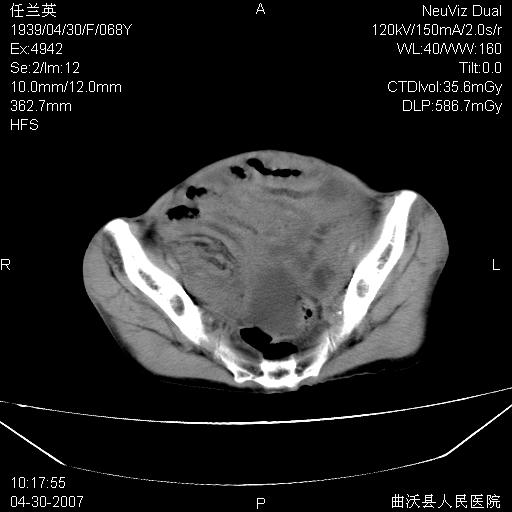

患者,女,68岁,感觉腹部憋涨发硬数天,查b超发现左盆腔有囊性肿物和少量腹水,行ct检查

支持左侧卵巢恶性肿瘤伴网膜、腹膜广泛转移。

支持:左侧卵巢恶性肿瘤伴网膜、腹膜 腹膜后(淋巴结)广泛转移。

网膜、腹膜广泛转移考虑来源于左侧卵巢癌可能性大。不除外来源于消化系的肿瘤。

难的一见 典型 - 网膜饼  冰冻骨盆 可以当教学片了